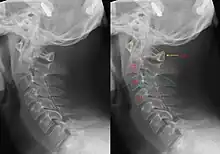

| CT scan of hangman's fracture | |

Hangman's fracture is the colloquial name given to a fracture of both pedicles, or partes interarticulares, of the axis vertebra (C2).[1]

Although a hangman's fracture is unstable, survival from this fracture is relatively common, as the fracture itself tends to expand the spinal canal at the C2 level. It is not unusual for patients to walk in for treatment and have such a fracture discovered on X-rays. Only if the force of the injury is severe enough that the vertebral body of C2 is severely subluxed from C3 does the spinal cord become crushed, usually between the vertebral body of C3 and the posterior elements of C1 and C2.